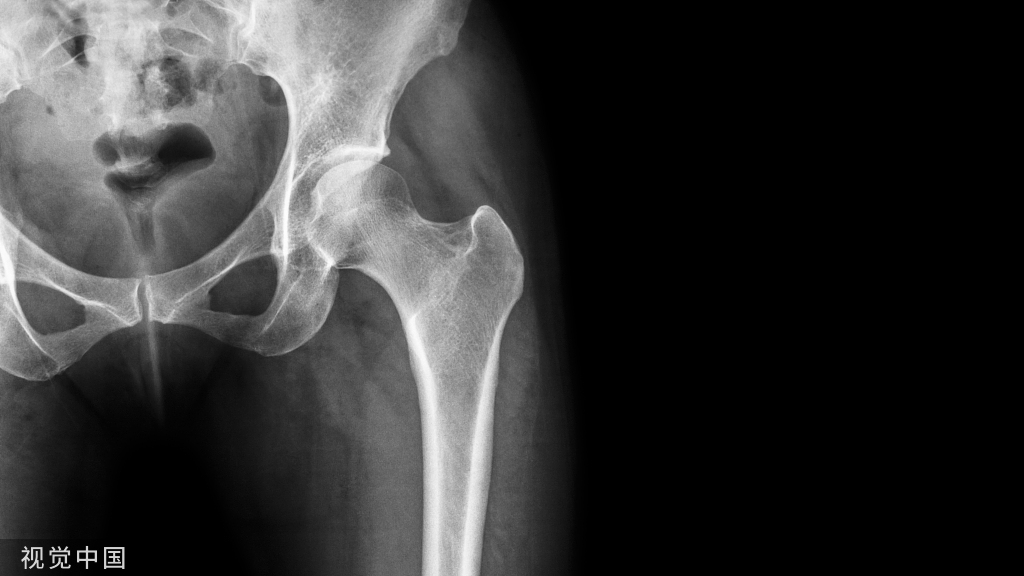

1950年,John Charnley 确立了人工关节低摩擦理论,提出并设计“金属-聚乙烯”全髋关节置换术假体,被誉为“现代人工髋关节置换之父”。

人工关节置换技术的成熟标志着骨关节外科进入置换外科时代其中以髋、膝关节置换技术最为成熟。在脊柱外科技术方面,越来越多的内固定器材或内镜系统进入临床并取得良好的效果。随着光纤技术的发展和小型手术器械的改进,关节镜的应用范围已经延伸到髋、踝、肩、肘、腕及颞下颌关节。